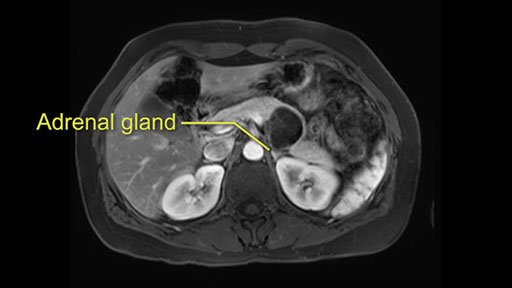

Tumor proximity to left adrenal gland

The lesion also is quite posterior. While the plane between the cyst and the left adrenal gland is often preserved, we do have to pay attention here so that we remain in the right plane and maintain our margin here. Occasionally in these cases, en bloc adrenalectomy needs to be performed.

Sometimes with even benign lesions of the spleen you can have quite a lot of inflammation in the retroperitoneum and so I do think about and wonder whether I will have some difficulty in the retroperitoneum and I usually look at the scan for that purpose. It looks like there is no inflammation in the retroperitoneum. It does look very close to the patient’s left adrenal gland but knowing the planes and suspecting that there isn’t any active inflammation, this should be able to come off the left adrenal gland without any difficulty. But obviously prepared to take some of the left adrenal if that’s necessary in this procedure. So those are my procedure-specific slowing down moments in a distal pancreatectomy when I’m considering a laparoscopic approach. I think the patient-specific slowing down moments in this particular case I have discussed with the procedure-specific moments. I don’t really see any other issue or that I have to be careful of or consider.

So first, I'll show you the scan. Here's the traditional view, where you see the cyst, which is in the body of the pancreas. And you see over here, it's got a quite thick wall. And going a little bit back also, here you see a septation which is very important, because I think a septation is what separates this from, for instance, the pseudocyst of the pancreatitis. And also the location of the cyst you see here, abutting the adrenal gland and going down a bit more, it's also quite close to a bowel loop. So when thinking about this cyst: female, the location in the body of the pancreas, thick wall, septation, and as you can read in history, it was basically asymptomatic, so no signs of pancreatitis. So, this probably all points towards a mucinous cystic neoplasm.